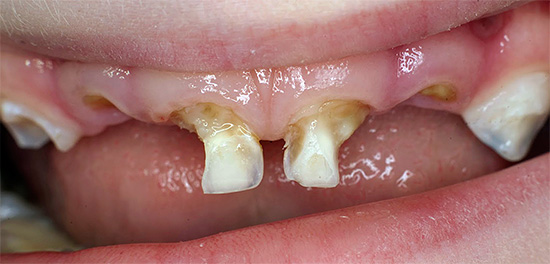

A destruição de até mesmo dentes de leite em uma criança pode levar a conseqüências não menos perigosas do que em adultos, e a dor de dente na infância geralmente é acompanhada de gritos e choro. Tentativas de alguma forma suportam uma dor de dente em casa, na esperança de que os dentes de leite caiam logo - esse é um grande erro dos pais e até, pode-se dizer, zombaria do bebê. Em alguns casos, atrasar uma visita ao dentista pode acabar com os dentes saudáveis da criança no futuro.

- Cárie, que em diferentes estágios pode se manifestar como dor fraca e que passa rapidamente, e dor bastante forte. Se você suprimir essa dor de dente em casa com pílulas, o processo de cárie inevitavelmente chegará à polpa, resultando em pulpite - e essa é uma dor muito mais intensa, e o tratamento desse dente estará associado à necessidade de remover o "nervo" dele. Geralmente, esse é um procedimento longo e caro, especialmente no caso de dentes multicanais.